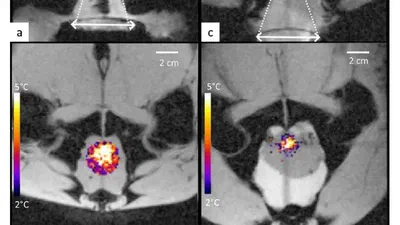

Abstract Radiofrequency (RF) ablation refers to a minimally invasive tumour ablation treatment using RF electromagnetic waves. A needle is placed inside the tumour, and an …